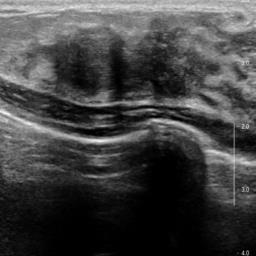

Ultrasonography is an important routine examination for breast cancer diagnosis, due to its non-invasive, radiation-free and low-cost properties. However, it is still not the first-line screening test for breast cancer due to its inherent limitations. It would be a tremendous success if we can precisely diagnose breast cancer by breast ultrasound images (BUS). Many learning-based computer-aided diagnostic methods have been proposed to achieve breast cancer diagnosis/lesion classification. However, most of them require a pre-define ROI and then classify the lesion inside the ROI. Conventional classification backbones, such as VGG16 and ResNet50, can achieve promising classification results with no ROI requirement. But these models lack interpretability, thus restricting their use in clinical practice. In this study, we propose a novel ROI-free model for breast cancer diagnosis in ultrasound images with interpretable feature representations. We leverage the anatomical prior knowledge that malignant and benign tumors have different spatial relationships between different tissue layers, and propose a HoVer-Transformer to formulate this prior knowledge. The proposed HoVer-Trans block extracts the inter- and intra-layer spatial information horizontally and vertically. We conduct and release an open dataset GDPH&GYFYY for breast cancer diagnosis in BUS. The proposed model is evaluated in three datasets by comparing with four CNN-based models and two vision transformer models via a five-fold cross validation. It achieves state-of-the-art classification performance with the best model interpretability.

翻译:超声波分析是乳腺癌诊断的一个重要常规检查,原因是其非侵入性、无辐射和低成本的特性。然而,由于其内在局限性,它仍不是乳腺癌的第一线筛选测试。如果我们能够精确地通过乳房超声图像诊断乳腺癌(BUS),它将是一个巨大的成功。我们提出了许多基于学习的计算机辅助诊断方法,以实现乳腺癌诊断/感官分类。然而,其中多数方法需要事先确定性能模型,然后对ROI内部的跨值进行分类。常规分类支柱,如VGG16和ResNet50等,可以在没有ROI要求的情况下实现有希望的分类结果。但是这些模型缺乏可解释性,从而限制了其在临床实践中的使用。在本研究中,我们提出了一个新的无乳腺癌诊断模型,在超声波图像中进行解释性特征描述。我们利用了先前的解剖学学学知识,即恶性肿瘤和良性肿瘤模型在不同组织层之间有着不同的空间关系,并提议采用状态解析法来编制这一先前的知识。拟议中的HOVer-Trans-Trading-Tradef-trainal Ex-deal-dealal-deal-deal-deal-degraphal-deal-deal-deal-deal-deal-deal disal disal-dal-dal-dal-dal-dal-deal-deal-dal-deal-deal-deal-dal-dal-dal-dal-dal-dal-dal-dal-dal-dal-dal-dal-dal-dal-I-dal-Iversal-dal-Ial-d-d-I-d-d-I-I-I-I-I-I-I-I-I-I-I-I-I-I-I-I-I-I-I-I-I-I-I-I-I-Ial-I-Ial-Ial-I-I-I-I-I-I-I-I-I-I-I-I-I-I-I-I-I-I-I-I-I-I-I-I-I-I-I-I-I-I-I-I-